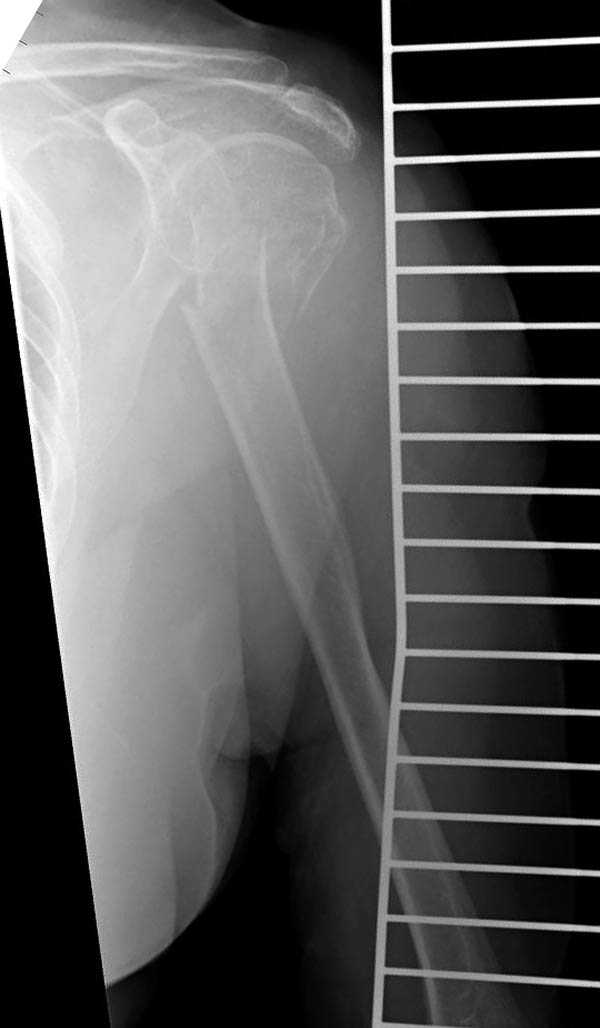

Второй случай, для лечения перелома проксимального

плеча применили пластину "Hand Innovation"

http://www.handinnovations.com/pdf/S3_technique.pdf

Пластина имеет преимущества перед другими "Locking

Implants", потому что пластину можно уложить намного ниже чем другие пластины и имеется возможности проведения шурупов под 130 градусным углом, таким образом можно уменьшить операционный разрез в проксимальной части.

Прооперирован вчера на 13 день после поступления.

Больному 41 и из-за гемодинамической нестабильности в течение первых 7 дней был в реанимации под интубационной седацией.